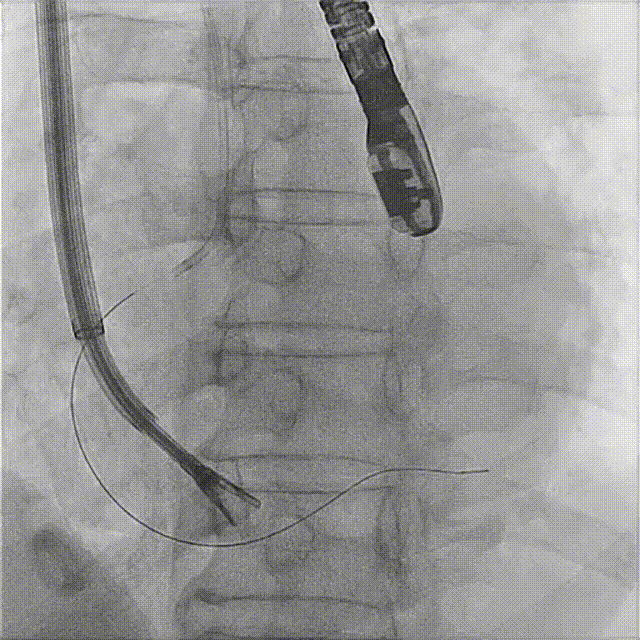

The second clip was deployed toward the septal leaflet, crossing the posterior‑septal commissure and positioned flush with the tricuspid annulus.

8. A second 14T device was selected and deployed following the same procedure.

During implantation of the second clip, anchoring was performed at the annulus near the leaflet base. Intraoperative DSA showed no impact on the coronary arteries, and good right coronary perfusion was confirmed after deployment.